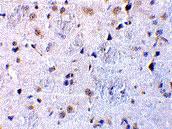

Immunohistochemical staining of rat brain tissue using CTRP7 antibody at 10 μg/mL. |